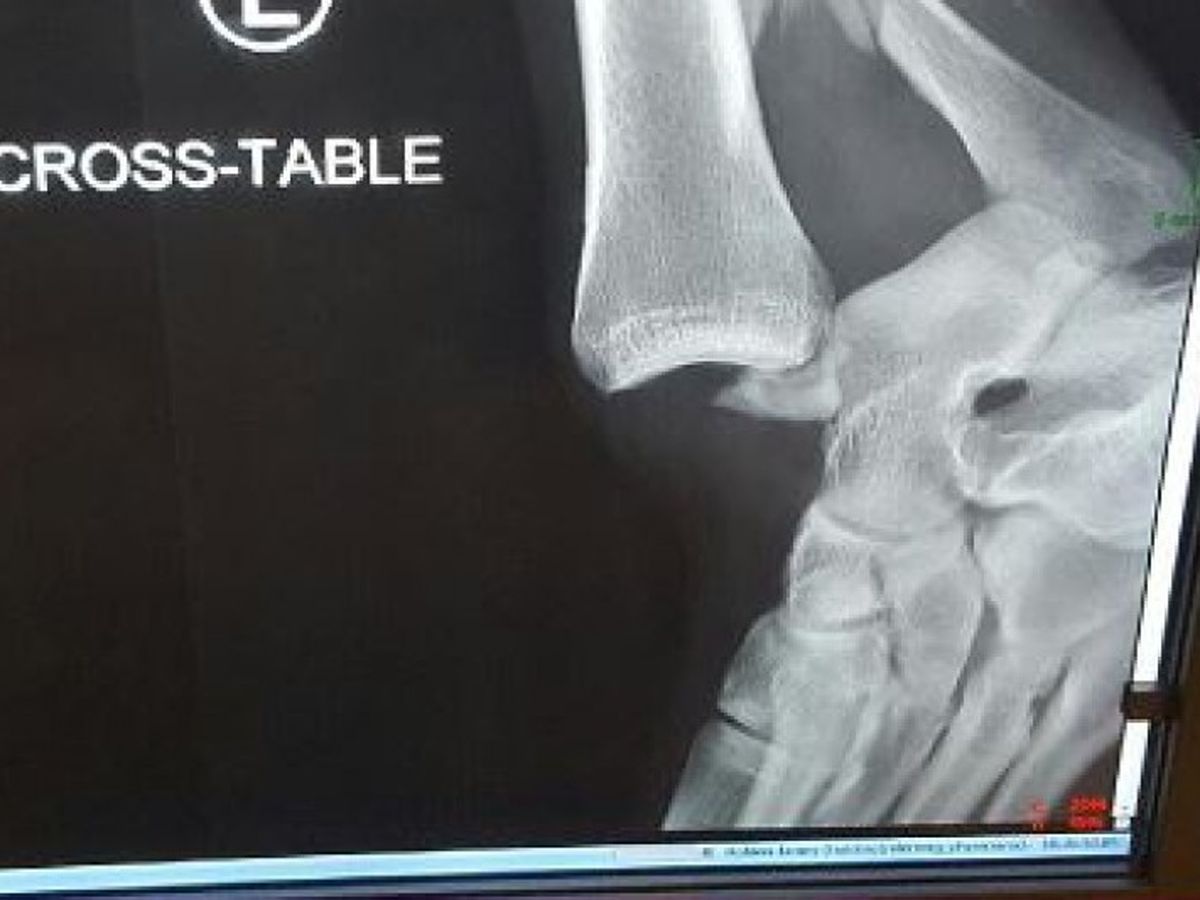

This is my son's ankle. He was on a creek here locally and helping a 12 year old little boy, slipped and fell, and severely severed his ankle. He has no insurance. When he went to the ER the doctors turned his foot around and sent him home, due to no insurance. He will be out of work for 3 to 6 months minimum and if he can't get an operation there's a good chance his foot will be amputated.

He is 27 years old and a construction worker. He has a young fiance with a 2 year old daughter and will need 24-7 care with no weight bearing for 3-6 months minimum. If not set and repaired he could be totally disabled at the very least for life. Please help to raise funds quickly so that doctors will operate and repair for his future. Surgery will consist of bare minimum screw and plating his bones together just to be able to walk again. Rehabilitation will be extensive if we can even get the surgery going.